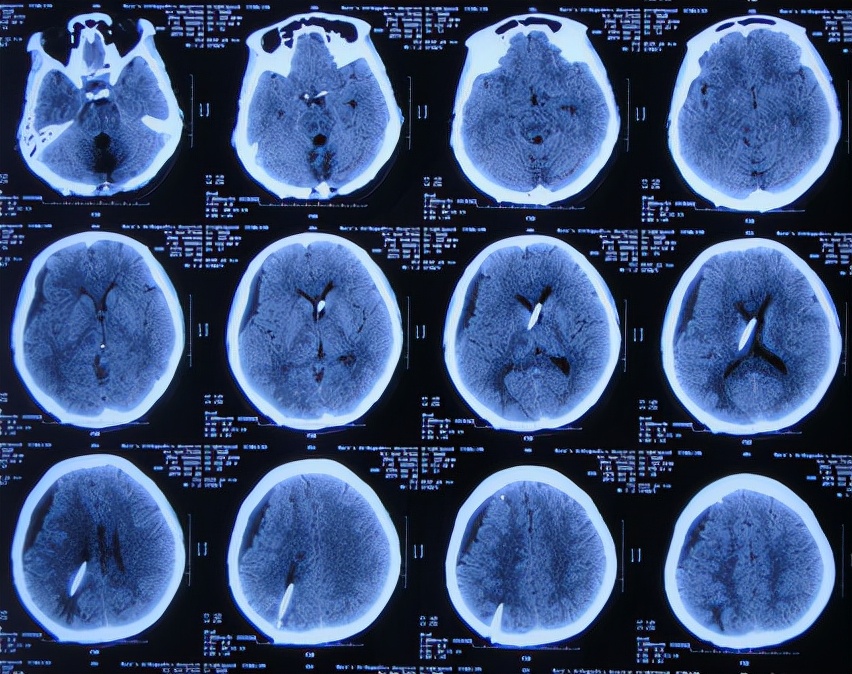

患者2019年2月18日下午,睡觉时突然出现剧烈头痛,持续无缓解,于是就诊于当地的山西省文水县某医院,查头颅CT示小脑出血破入脑室( 图-1 );考虑出血量不多,住院保守治疗。

图-1: 2019年2月18日头颅CT